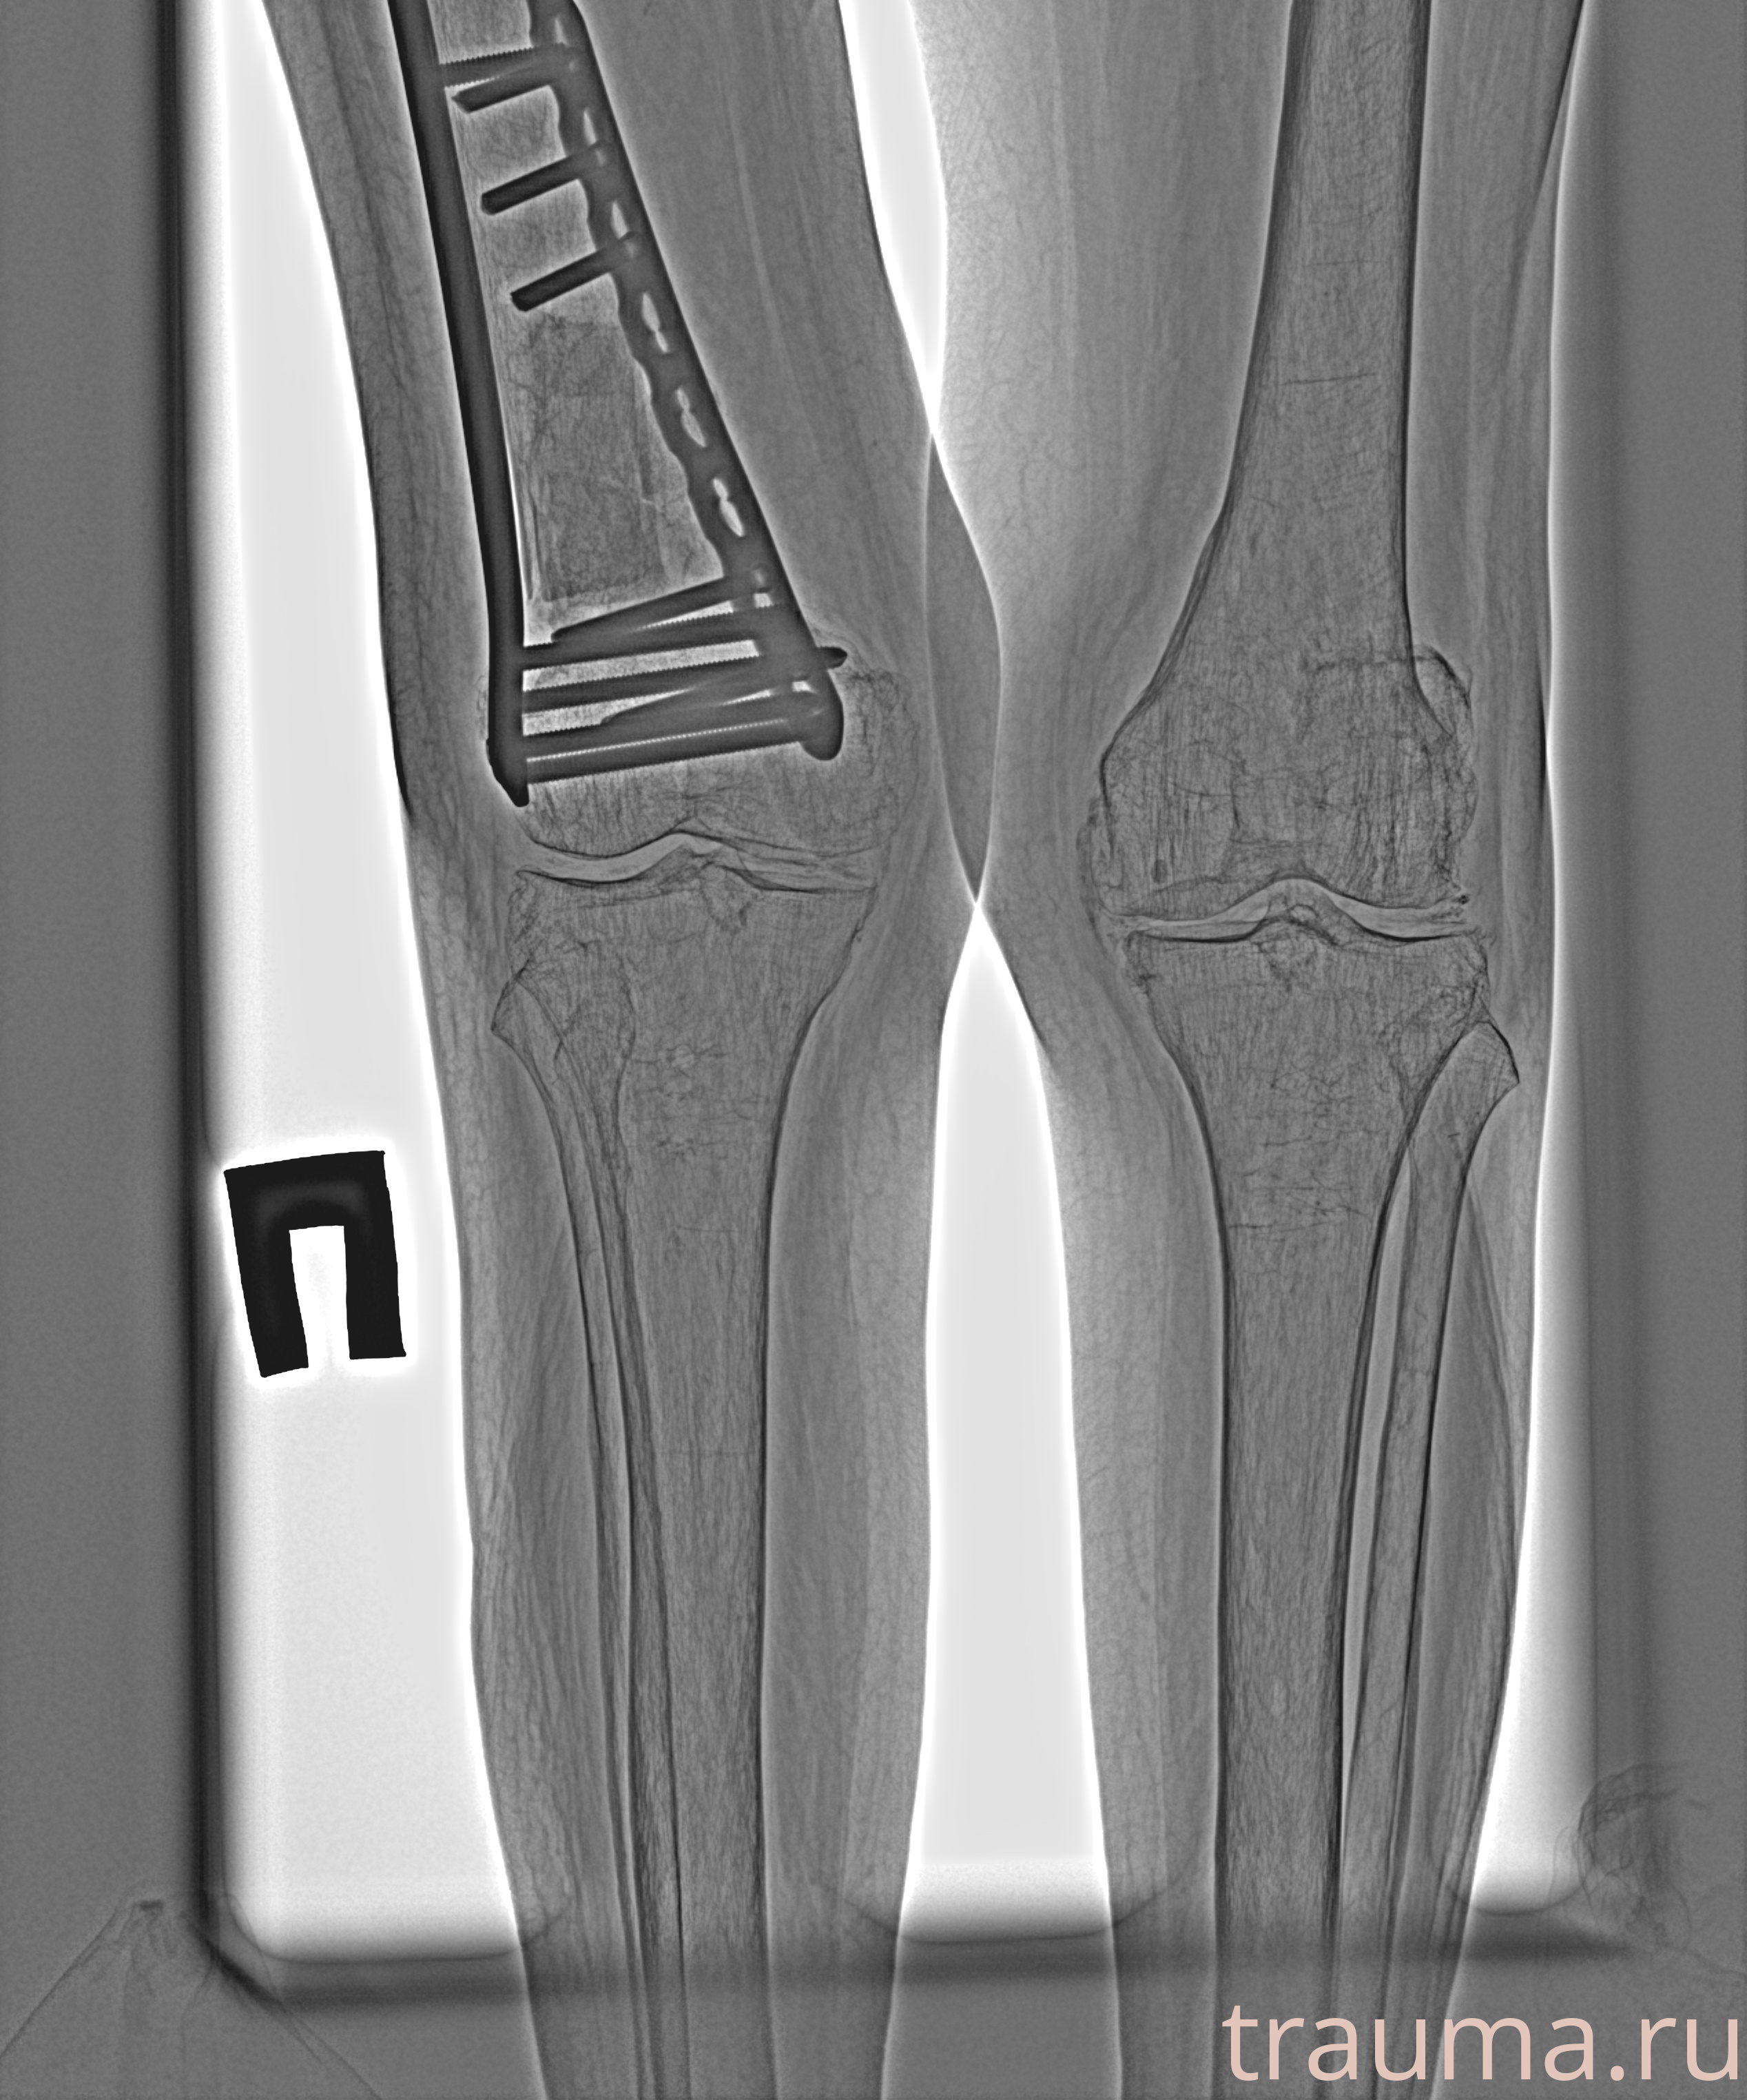

Рентгенограммы